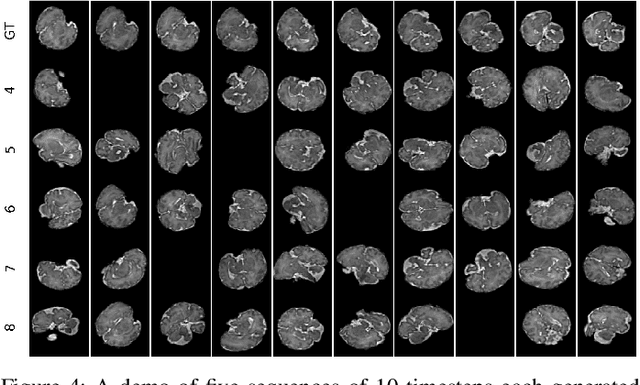

Fetal magnetic resonance imaging (MRI) is challenged by uncontrollable, large, and irregular fetal movements. Fetal MRI is performed in a fully interactive manner in which a technologist monitors motion to prescribe slices in right angles with respect to the anatomy of interest. Current practice involves repeated acquisitions to ensure diagnostic-quality images are acquired; and the scans are retrospectively registered slice-by-slice to reconstruct 3D images. Nonetheless, manual monitoring of 3D fetal motion based on displayed 2D slices and navigation at the level of stacks-of-slices (instead of slices) is sub-optimal and inefficient. The current process is highly operator-dependent, requires extensive training, and significantly increases the length of fetal MRI scans which makes them difficult for pregnant women, and costly. With that motivation, we presented a new real-time image-based motion tracking technique in MRI using deep learning that can significantly improve state of the art. Through a combination of spatial and temporal encoder-decoder networks, our system learns to predict 3D pose of the fetal head based on dynamics of motion inferred directly from sequences of acquired slices. Compared to recent works that estimate static 3D pose of the subject from slices, our method learns to predict dynamics of 3D motion. We compared our trained network on held-out test sets (including data with different characteristics, e.g. different age ranges, and motion trajectories recorded from volunteer subjects) with networks designed for estimation as well as methods adopted to make predictions. The results of all estimation and prediction tasks show that we achieved reliable motion tracking in fetal MRI. This technique can be augmented with deep learning based fast anatomy detection, segmentation, and image registration techniques to build real-time motion tracking and navigation systems.